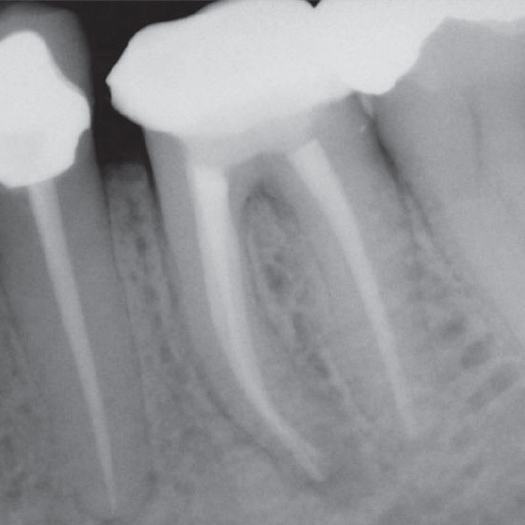

After

After Root Canal treatment